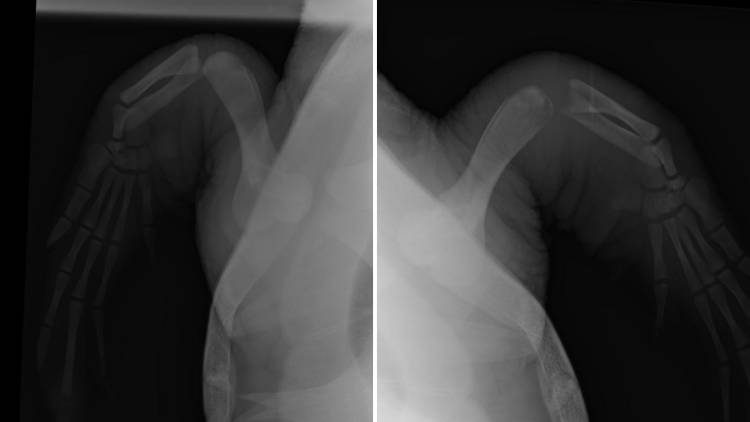

X-rays comparing Nobomvu's healthy flipper (left) to the infected one (right). Note the degradation of her "elbow" joint.

X-rays and joint samples were taken, revealing that Nobomvu has osteomyelitis, nd infection of the bone, in her right flipper. Osteolytic (bone-eating) lesions in sea turtles have been identified as a secondary effect of traumatic injuries and compromised immune systems, and we know that the stress of being stranded, as well as the injuries associated with entanglement, can and do leave sea turtles immunocompromised. Due to the slow metabolisms of sea turtles, secondary infections like this only become evident much later than we would expect in mammals.